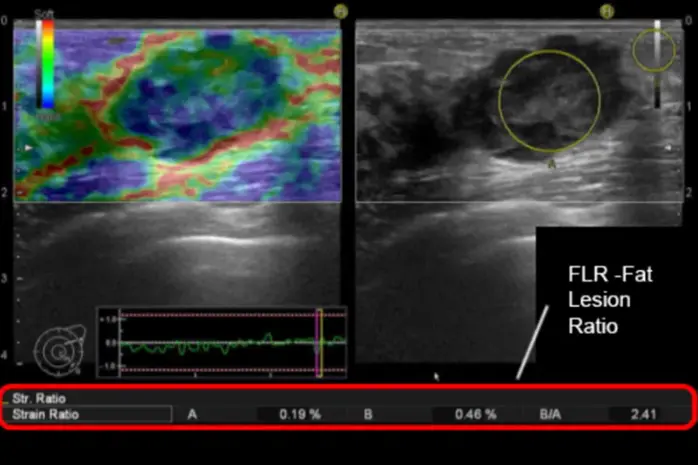

Elastography is a diagnostic method that provides information about tissue stiffness and overlays this information onto morphological images, most commonly in the form of a transparent color map.

Tissue stiffness can be assessed using two main approaches:

- Observation of tissue deformation in response to external mechanical forces (Strain Elastography).